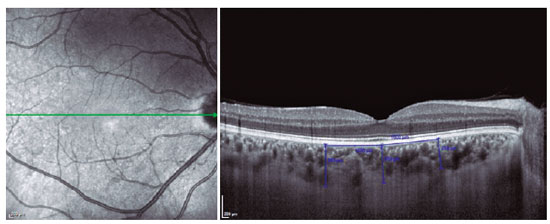

Choroidal thickness was measured from the outer portion of the hyperreflective line, corresponding to the retinal pigment epithelium, to the inner surface of the sclera. The choroidal thickness measurements were made at the following 3 points: at the subfovea, 1500 µm nasal to the fovea, and 1500 µm temporal to the fovea (Figure 1). EDI-OCT images were recorded at the same time of the day (9:00 am to 12:00 pm) to avoid the influence of diurnal variations. All the measurements were performed by 2 independent masked observers at baseline and 4 months after remission.

12-fig01tb.jpg)